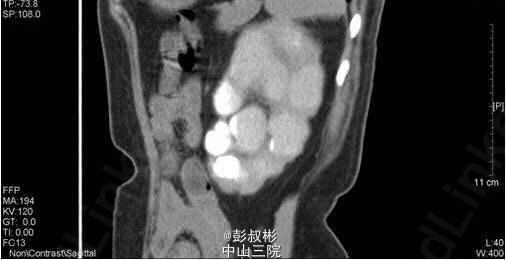

1、因“反复下腰部胀痛伴发热2月,加重10天” 入院。入院前最高体温39.5℃ ,外院检查尿隐血及尿白细胞3+,进一步行泌尿系B超显示双肾及左输尿管下段结石,左肾重度积液 。 2、既往史: 10年前因肾结石行体外冲击波碎石术,自诉术后恢复良好。 3、辅助检查:1) 血常规(抗炎后)、血生化(补钾后)、肝功、凝血、术前八项、胸片及心电图未见明显异常; 2) 尿常规:12.9 :尿液白细胞+++ 尿液红细胞++ 左肾造瘘液白细胞++ 左肾造瘘液红细胞++ 3) 真菌培养:无真菌生长 4) 肾功能:12.9: 肌酐5.68 mmol/L尿素氮: 186 nmol/L 5) 核素肾动态显像+GFR双血浆测定 1.右肾灌注、功能中度受损,右上尿路慢性梗阻。 2.左肾灌注、功能中度受损,左上尿路机械性梗阻。 灌注相:双肾于腹主动脉显影后2秒开始显影,放射性灌注明显减低(右肾明显低于左肾)。灌注曲线分析:双肾灌注峰明显减低。 功能相:右肾影稍增大,放射性摄取明显减低,放射性分布不均匀,可见多发放射性分布稀疏缺损区,放射性排泄缓慢。左肾增大,放射性摄取减低,放射性分布不均匀,可见多发放射性分布稀疏缺损区,放射性排泄缓慢,左肾盏见明显放射性滞留。半小时内膀胱可见放射性积聚。 肾图:右肾a段降低,b、c段融合为低水平延长型肾图。左肾a段降低,b、c段融合为持续上升型肾图。双血浆法肾小球滤过率(GFR)左肾为19.7ml/min,右肾GFR为17.9ml/min。 6) 双肾CTU平扫+增强螺旋扫描 1、左肾多发结石、重度积液、肾功能减退,左输尿管膀胱入口处结石,左侧输尿管炎症; 2、右肾多发结石、轻度积液,右肾功能减退,右肾盂及输尿管炎症。 4、诊断:双肾积脓 右肾铸形结石 左肾多发结石 左输尿管下段结石碎石术后 双肾功能减退 5、入院后处理:予以“舒普深” 3.0 Bid 抗感染,12-5 行“B超引导下经皮左肾穿刺造瘘术”,每日引流出约1500ml脓液。肾功能改善后于12-9行“左侧输尿管镜下钬激光碎石取石术”,术程顺利,术后予以舒普深3.0 Bid抗感染,体温正常。昨日下午行“B超引导下经皮右肾穿刺造瘘术”。